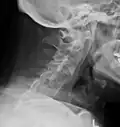

The earliest changes demonstrable by plain X-ray shows erosions and sclerosis in sacroiliac joints. Progression of the erosions leads to widening of the joint space and bony sclerosis. X-ray spine can reveal squaring of vertebrae with bony spur formation called syndesmophyte. This causes the bamboo spine appearance. A drawback of X-ray diagnosis is the signs and symptoms of AS have usually been established as long as 7–10 years prior to X-ray-evident changes occurring on a plain film X-ray, which means a delay of as long as 10 years before adequate therapies can be introduced.[25]

Lateral X-ray of the neck in ankylosing spondylitis